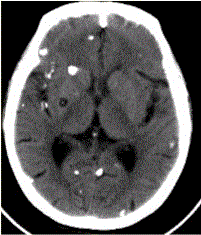

问题 患者男,45岁。头痛、癫痫10余年。查体:无发热,双侧肢体肌力正常。脑电图示双侧额颞叶棘波放电。CT表现如下图。 初步拟诊为(提示MR表现如下图:既往在内蒙古生活7年。)

选项 A.脑包虫 B.结核瘤 C.转移瘤 D.脑囊虫 E.多发性硬化 F.脑脓肿 G.腔隙性梗死

答案 D